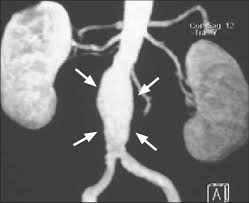

Temos um aneurisma da aorta abdominal quando essa artéria atinge um diâmetro 50% maior do que o esperado, sendo que o seu diâmetro máximo normal é de 2,0 cm. Um diferencial é que o profissional também poderá solicitar um ecocardiograma, já que aneurismas torácicos costumam estar perigosamente relacionados com o coração. No entanto, caso a artéria se rompa, será necessário um diagnóstico rápido e cirurgia de emergência. Ocorre quando a parede da aorta abdominal se torna enfraquecida e a pressão continuada do sangue que corre através da. O que é a artéria aorta?

A aorta é o maior vaso sanguíneo do corpo; O que é um aneurisma da aorta abdominal. Aneurisma da aorta abdominal (aaa), é uma dilatação anómala na porção abdominal da artéria aorta de tal modo que o diâmetro ultrapassa os 3 cm ou atinge um diâmetro 50% maior do que o normal. Aneurismas da aorta abdominal geralmente não apresentam sintomas, mas uma sensação pulsante no abdômen e / ou no dorso tem sido descrita. O que é aneurisma1 de aorta abdominal3?

Aspectos do diagnóstico e tratamento do aneurisma da aorta abdominal. Um aneurisma da aorta abdominal é justamente um aneurisma que se estabelece neste último trecho da aorta. Isto significa que tem um aneurisma da aorta abdominal médio. A pressão do interior da artéria faz com que a área enfraquecida fique protuberante além da largura normal do vaso sanguíneo. O que é um aneurisma? Sempre que existir suspeita de aneurisma ou de rompimento de um aneurisma é muito importante ir imediatamente ao hospital, para fazer os os sintomas de aneurisma de aorta abdominal são mais raros que os da aorta torácica, mas ainda assim pode surgir: Um aneurisma da aorta abdominal é um edema localizado e inchaço na parte inferior da aorta devido ao enfraquecimento da parede do vaso. Pesquisa afirma que aneurisma da aorta abdominal é de 3 a 7 vezes mais frequente que aneurisma na aorta torácica.

O aneurisma 1 é uma dilatação localizada e permanente da parede de um grande vaso sanguíneo, causado na maioria das vezes por enfraquecimento da parede do vaso, pela pressão do fluxo sanguíneo ou por uma inflamação 2. Um aneurisma da aorta abdominal é justamente um aneurisma que se estabelece neste último trecho da aorta. Ocorre quando a parede da aorta abdominal se torna enfraquecida e a pressão continuada do sangue que corre através da. O aneurisma mais comum da aorta é um aneurisma aórtico abdominal (aaa). Temos um aneurisma da aorta abdominal quando essa artéria atinge um diâmetro 50% maior do que o esperado, sendo que o seu diâmetro máximo normal é de 2,0 cm. A maioria dos pacientes são assintomáticos, excepto quando o aneurisma se rompe. O aneurisma pode causar dor, normalmente uma dor profunda e penetrante, principalmente nas costas. La aorta es el principal vaso sanguíneo que irriga el abdomen, la pelvis y las piernas. Por mais que um aneurisma de aorta abdominal possa ser fatal em caso de rompimento, a novidade é que o tratamento eficaz pode impedir que isso ocorra. Essa dilatação é causada pela perda de. Isso ocorre na parte da aorta que atravessa o abdômen. Para usar os recursos de compartilhamento desta página, ative o javascript. Ao compreender os fatores de risco, sintomas e opções de tratamento, você poderá se preparar para agir rapidamente se necessário.